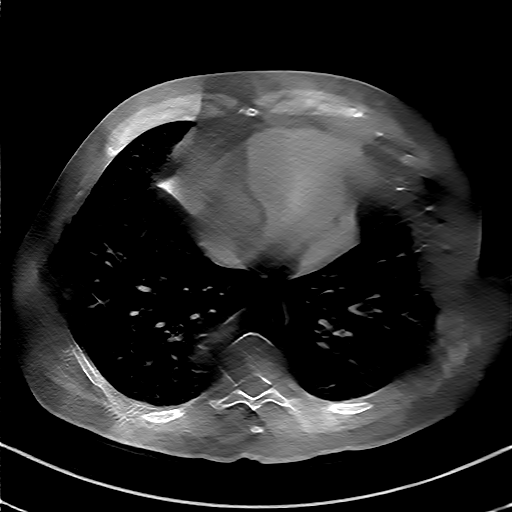

GT

FBP

HQS-CG

DuDoNet

Meta

Meta_re

EPNet

Qualitative Results Comparison. We also visualize the reconstruction results of these methods on AAPM-test and COVID-test datasets. As in the first three rows of Fig. 4, the reconstructed images from ours and retrained MetaInvNet show the best visualization quality on AAPM-test set across different angle numbers. Besides, our results show sharper details with the additional utilization of in the projection domain. When testing the reconstructed image on the COVID-test set, our result also gives sharper details but with more artifacts since the data distribution is very different. Although HQS-CG has achieved better quantitative results on the COVID-test dataset, the reconstructed image of their model in the fourth row is even smoother than FBP.